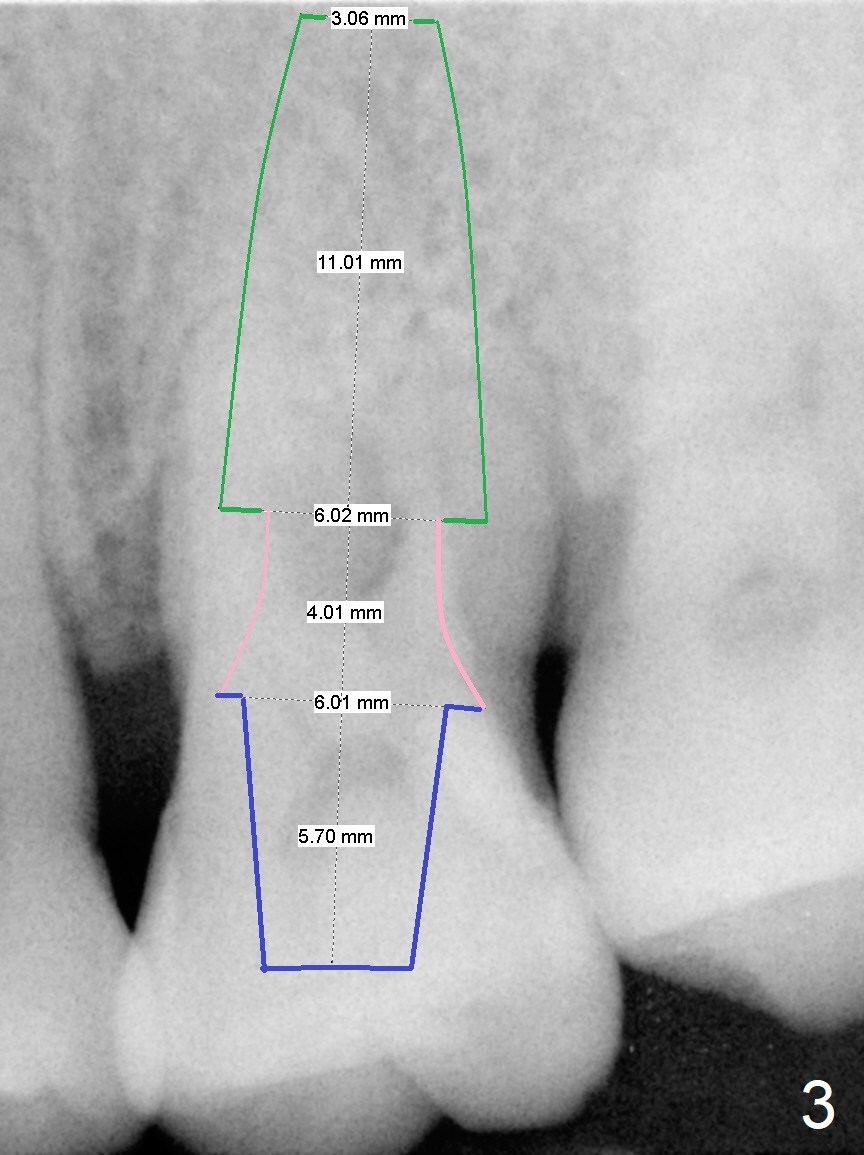

A 44-year-old man is a typical patient with chronic periodontitis (Fig.1).  Periimplantitis develops following immediate implant at #31 (Fig.2).  The symptom (bleeding) improves after bone graft and use of Water Pik.  Now the tooth #14 appears to be non-salvageable because of gingival hemorrhage and deep pockets after previous osseous surgery.  To prevent periimplantitis, an immediate implant does not need to be large or long.  It has to be placed deep, and in the middle of the native bone, surrounded by bone graft.  To facilitate wound healing, draw 3 tubes of blood for PRF.  One of them is processed for plug in case of sinus lift.  To prevent the buccal gingiva collapse, the buccal portion of the immediate provisional should extend into the socket.  If the gingiva is around 4 mm, use IBS implant (Fig.3,4).  Otherwise, a SM implant will be used after extraction (Clindamycin), since abutments have cuffs as long as 4.5 and 6 mm so that it is easy to place an implant as deep as possible.  Initial depth will be 9 mm (bone-level), followed by Magic Drill (5.3 mm, if possible) and Magic expanders (4.3x10 and 4.8x11 mm, bone density 26-300 units).